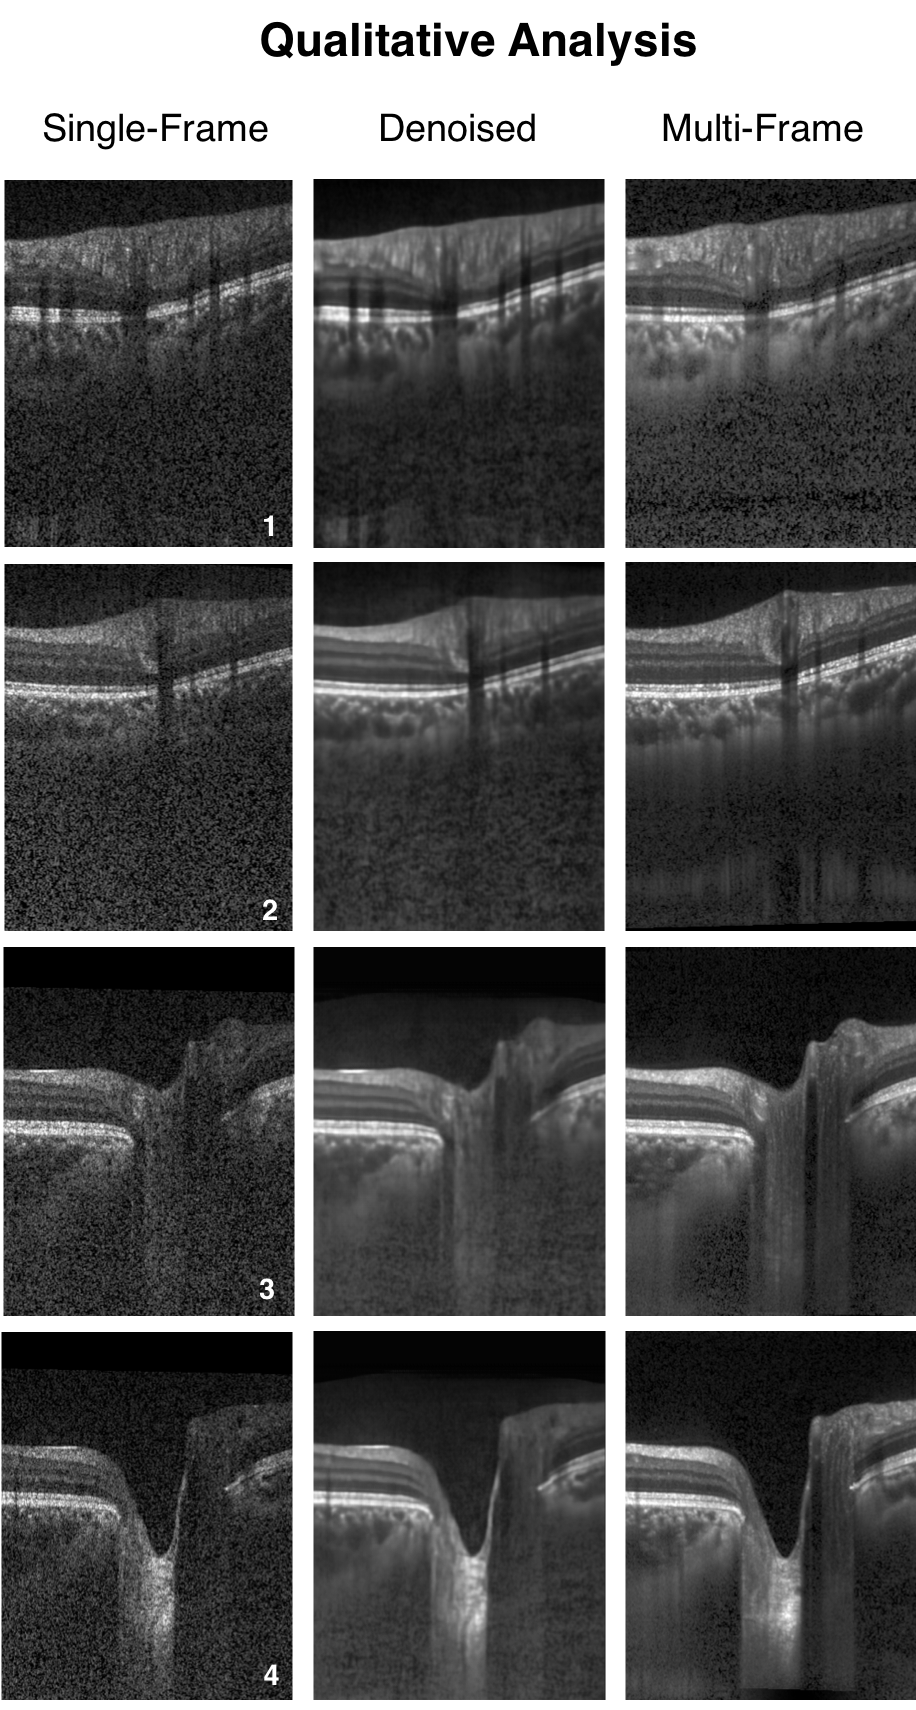

When trained with the ‘clean’ B-scans (multi-frame) and the corresponding ‘noisy’ B-scans, our network was able to successfully denoise unseen single-frame B-scans. The single-frame, denoised and multi-frame B-scan for a healthy subject can be found in (Figure 3). In all the cases, the denoised B-scans were qualitatively similar to their corresponding multi-frame B-scans (Figure 4). Overall, the visibility of all ONH tissues were prominently enhanced (Figure 3; B).

Refer to caption

Figure 4: Single-frame, denoised and multi-frame B-scans for four healthy subjects (1-4) are shown. In all cases, the denoised B-scans (2nd column) were consistently similar (qualitatively) to their corresponding multi-frame B-scans (3rd column).

Using the proposed network, we obtained denoised B-scans that were qualitatively similar to their corresponding multi-frame B-scans (Figure 3) and (Figure 4), owing to the reduction in noise levels. The mean SNR for the denoised B-scans was 8.14±1.03plus-or-minus8.141.038.14\pm 1.03 dB, a two-fold improvement (reduction in noise level) from improvement from 4.02±0.68plus-or-minus4.020.684.02\pm 0.68 dB that was obtained for the single-frame B-scans, thus offering an enhanced visibility of the ONH tissues. Given the significance of the neural (retinal layers) [79, 80, 81, 82, 83] and connective tissues (sclera and LC) [84, 85, 86, 87, 88], in ocular pathologies such as glaucoma [2], and age-related macular degeneration [89], their enhanced visibility is critical in a clinical setting. Furthermore, reduced noise levels would likely increase the robustness of aligning/registration algorithms used to monitor structural changes over time [18]. This is crucial for the management of multiple ocular pathologies [90, 91].